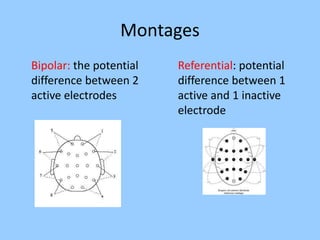

3. International standards for EEG electrode placement and recording parameters are reviewed. Characteristics of different EEG waves, amplitudes, and patterns are described.